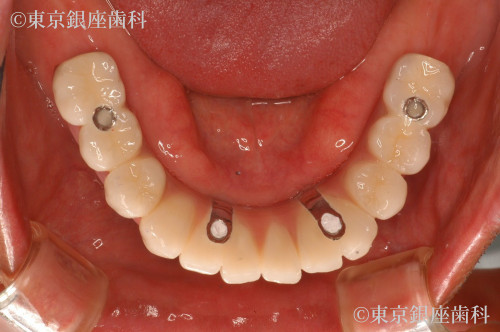

ボロボロの歯の症例

30代 男性

疾患 歯周病

施術内容 ワンデイインプラント

治療期間 8カ月 費用 630万円(税込)

虫歯、歯周病

上下ワンデイインプラント